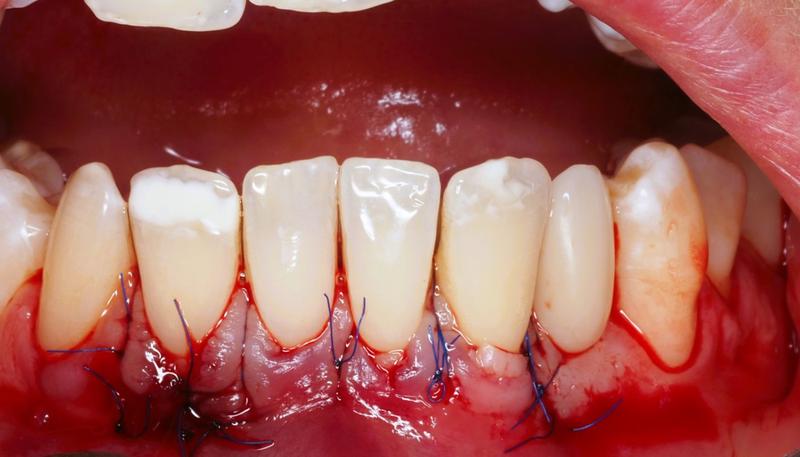

Na koniec, nie zapominaj o regularnych wizytach u dentysty. Specjaliści z dziedziny stomatologii najlepiej znają się na zdrowiu zębów. Choć może wydawać się to mało romantyczne, regularne kontrole są kluczem do uniknięcia poważniejszych problemów. Zainwestuj w profesjonalne higienizacje, a w razie potrzeby skorzystaj z terapii laserowej czy nowoczesnych materiałów kompozytowych, które skutecznie zamkną odsłonięte szyjki. Czy może być coś lepszego niż uśmiech, który nie przynosi bólu?

Jednak nie wszystko stracone! Kluczem do sukcesu pozostaje wczesna interwencja oraz nauka odpowiednich nawyków higienicznych. Miękka szczoteczka oraz technika „wymiatania” mogą zdziałać prawdziwe cuda. A jeśli mycie zębów staje się bolesne, warto zainwestować w specjalne pasty, które łagodzą nadwrażliwość. Zdarzyło się Wam kiedykolwiek spojrzeć na reklamę idealnego uśmiechu i pomyśleć: „Chcę tak wyglądać!”? W takim razie czas udać się do dentysty i postawić na zdrowie dziąseł – bo piękne zęby to nie tylko kwestia estetyki, ale i fundament, na którym opiera się nasz uśmiech!